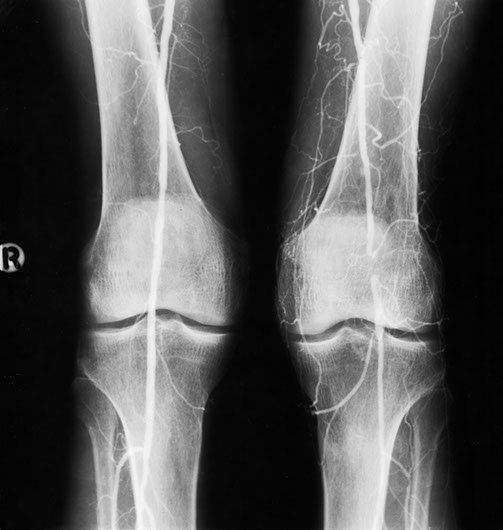

This patient developed several strictures two years apart. This one is a popliteal stricture.

Popliteal stricture post dilatation

And this represents the second stricture two years later in the left lower femoral artery

And this is the post-dilatation image of the femoral stricture.